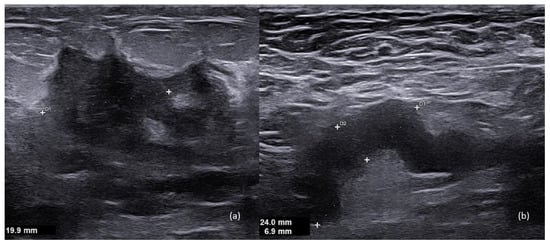

4. Imaging